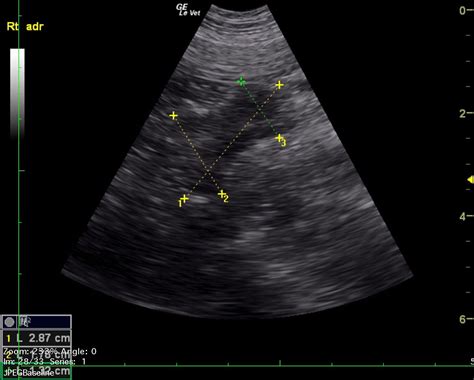

Imaging Studies

To determine the physical characteristics of the mass, the following imaging studies may be used:

- CT Scan (Computed Tomography): Often the first-line imaging modality to assess the size and appearance of the mass.